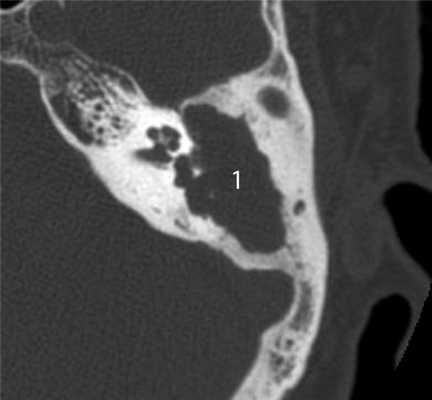

Главными отличительными признаками костной деструкции опухолевого генеза являются беспорядочность и широкая распространенность (рис. 4). Рисунок 4. Лангергансоклеточный гистиоцитоз. Аксиальная проекция правой височной кости. Распространенные беспорядочные деструктивные изменения остеолитического характера (1) в пирамиде и сосцевидном отростке. Мягкотканное образование (2) выполняет барабанную полость, обтурирует наружный слуховой проход. Участки костной деструкции могут быть выявлены на КТ в сосцевидном отростке, наружном слуховом проходе, в стенках барабанной полости и антрума, в капсуле лабиринта, в пирамиде височной кости и за ее пределами в костях основания и свода черепа [2, 4, 5]. Чем раньше обследуется ребенок с опухолью среднего уха, тем менее распространена деструкция в височной кости. Самые ранние стадии опухолевого процесса характеризуются ее отсутствием, что крайне затрудняет установление диагноза.

КТ-симптоматика параганглиомы или гломусной опухоли височной кости, редко встречающейся у детей, включает нарушение пневматизации полостей среднего уха в сочетании с костной деструкцией (рис. 7, а). Рисунок 7. Гломусная опухоль. а — аксиальная проекция правой височной кости. В пирамиде височной кости определяется объемное образование, вызывающее разрушение стенок ямки луковицы яремной вены (1) и канала внутренней сонной артерии (2). Поскольку параганглиома исходит из яремного и, реже, каротидного гломуса, ее отличительным КТ-признаком является деструкция стенок ямки луковицы яремной вены и канала сонной артерии [5—7]. В отличие от злокачественных опухолей, параганглиома активно накапливает контрастный агент при внутривенном введении в артериальную фазу (рис. 7, б). Рисунок 7. Гломусная опухоль. б — коронарная проекция левой височной кости, внутривенное болюсное контрастирование, артериальная фаза. В барабанной полости определяется опухоль (1), активно накапливающая контрастный агент. Практически одинаковая интенсивность накопления контрастного вещества в ткани опухоли и во внутренней сонной артерии (2).